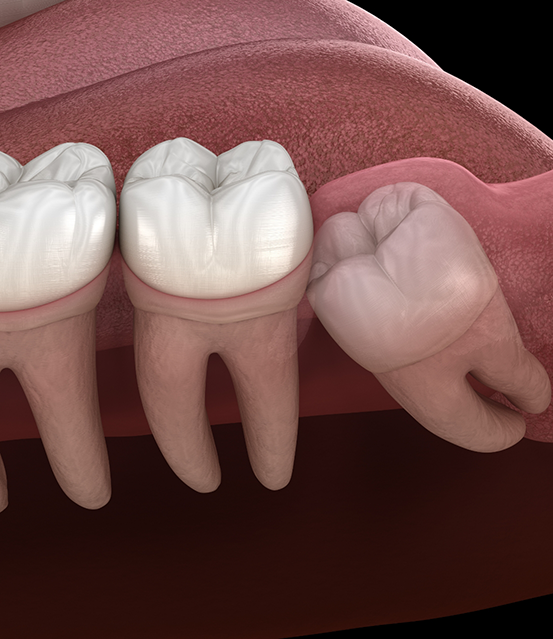

Wisdom teeth, or third molars, can erupt in your late teens and early twenties. Sometimes, these molars do not have enough room to come in properly. It might lead to crowding and infection. Here are some common reasons to get it removed:

- A trapped or partially erupted wisdom tooth can push against your neighboring teeth. You might experience swelling, chronic discomfort, and cysts if left untreated.

- The third molars can damage or shift your second molars. Lack of enough space might lead to root damage and alignment problems.